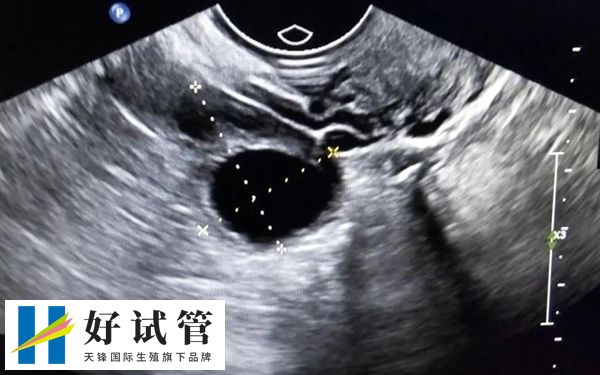

试管婴儿通常在女性双侧卵巢取卵,因为卵巢是女性的生殖器官,其主要功能之一是产卵。女性做取卵手术时,医生会从阴道后穹窿拿一根长长的穿刺针进入盆腔。在超声波的指导下,穿刺针到达卵巢,针对卵泡取卵。

卵巢的正常位置应该在子宫两侧,而少部分患者可能存在盆腔炎症和粘连,卵巢的位置发生了改变,有的紧贴盆腔内大血管,有的位于子宫顶上,平时做超声监测卵泡时,位置不太好找,取卵时可能会给医生增加难度。

如果卵巢临近大血管,我们首先考虑安全第一,能取的尽量都取完,不能取的就不冒险而为。如果卵巢处于子宫顶上,可能穿刺针要穿过子宫或者膀胱,穿过膀胱后可能排小便会有不适感,但是一般恢复比较快。